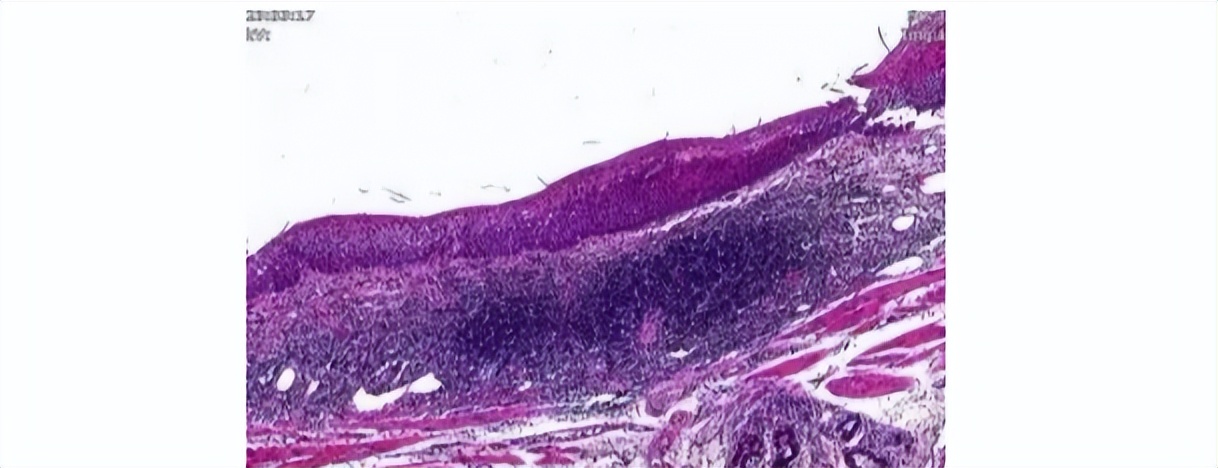

结果胃镜显示,距门齿25cm-30cm见不规则片状黏膜略粗糙,初步怀疑为食管癌。随后,食管活检病理证实了这个猜想。

这两项可以较为直观地看到癌细胞,在临床诊断、术后随访、疗效观察上都是最可靠的方法。早期食管癌中,检出率高达85%以上。